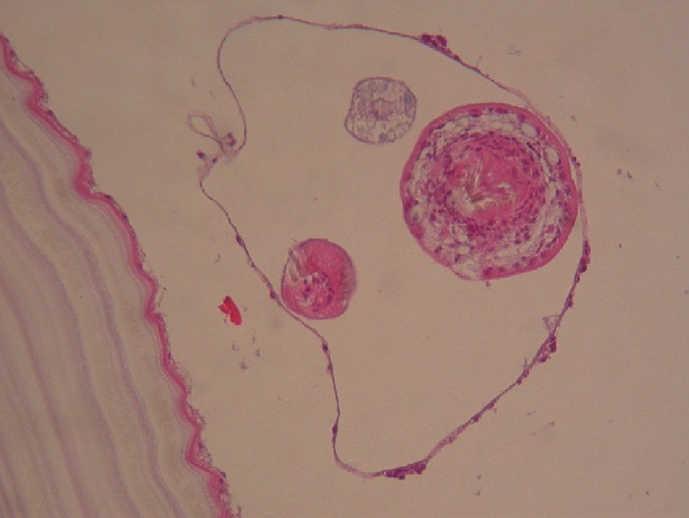

Figura 4.Corte histológico en el que se visualiza Echinoccoccus granulosus.

El estudio anatomopatológico informó de un nódulo intramural quístico de 7 cm de diámetro, con luz repleta de líquido seroso y vesículas de hasta 2 cm. Al microscopio se observó un material laminar anhisto, eosinófilo y acelular que se rodeaba externamente por tejido de granulación fibroso. El diagnóstico fue de quiste hidatídico intramural, sin otros hallazgos histológicos significativos en la pieza operatoria.